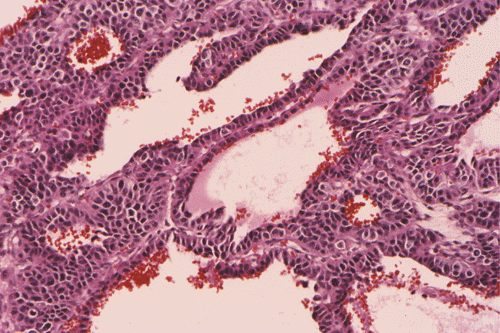

Clinical information: The patient was a 17 year-old boy who was in good health and was an active basket ball player. There was no history of asthma or other major illness. He developed chronic cough, wheezing and shortness of breath about 13 months before presentation.  The patient was initially treated in an outside facility under the clinical impression of asthma and his condition improved. Two months before presentation to our institution, he developed fever spikes with worsening of his cough and sputum production. There was also a weight loss of 10 pounds. His pulmonary function tests showed an obstructive pattern with both inspiratory and expiratory abnormal flow volume loops suggestive of variable intrathoracic airway obstruction. The PPD test was negative. A chest x-ray revealed mild atelectasis in the right upper lobe. A bronchoscopy was performed and a biopsy was taken. Based on the pathology results of the biopsy, a lobectomy of the right upper lobe was performed. The following photographs were taken from representative areas of the surgically resected specimen.

What is your histologic diagnosis?  Discussion